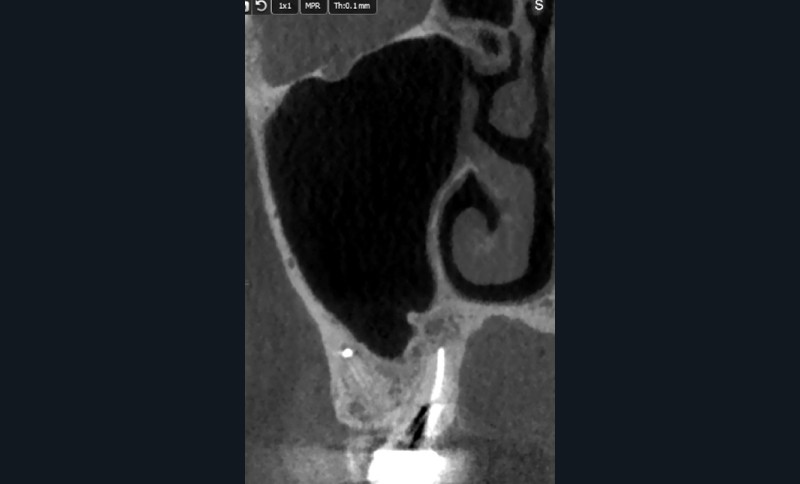

Rebondissant sur l’imagerie 3D et la mise en évidence des anatomies canalaires complexes, Peters, en 2001, décrit l’insuffisance instrumentale dans le traitement endodontique, et montre que 35 % des surfaces sont intactes après préparation canalaire correctement menée [18].

Endal, en 2011, montrait également, en utilisant le micro CT Scanner, l’insuffisance de nettoyage des isthmes inter-canalaires à nos techniques conventionnelles [19]. L’utilisation du laser Er:YAG devenait alors incontournable dans le nettoyage de ces isthmes et des zones non instrumentées (fig. 2 et 3).

Cette pénétration s’étend de la chambre pulpaire au réseau canalaire, isthmes, deltas apicaux et tubulis dentinaires. Il a été démontré que l’effet de cavitation pourrait permettre la destruction des bactéries à des profondeurs de 300 à 400 µm au sein des surfaces irradiées [20].

L’anatomie complexe du système canalaire et la pénétration difficile des irrigants [26] limitent la capacité de nettoyer, débrider, et désinfecter en trois dimensions le réseau endodontique.

L’un des problèmes majeurs en endodontie reste les contraintes inhérentes à la dynamique des fluides, dans un espace canalaire confiné [27]. Ce phénomène physique empêche, en l’absence de turbulence, l’irrigant d’être véhiculé dans la zone apicale [28] et dans les zones non instrumentées et d’exercer son action solvante et antibactérienne.

Si l’étude de Peters [18] nous montre que l’instrumentation laisse 35 % du volume canalaire non instrumenté, Ricucci et Siqueira montrent que la préparation physico-chimique n’élimine que partiellement les tissus nécrotiques à l’entrée des canaux latéraux, des isthmes et des ramifications apicales, en laissant des tissus enflammés et infectés, en association avec des lésions apicales [29] (fig. 4 et 5).